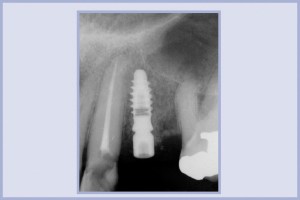

- Fig. 39 – Controllo radiografico post-operatorio